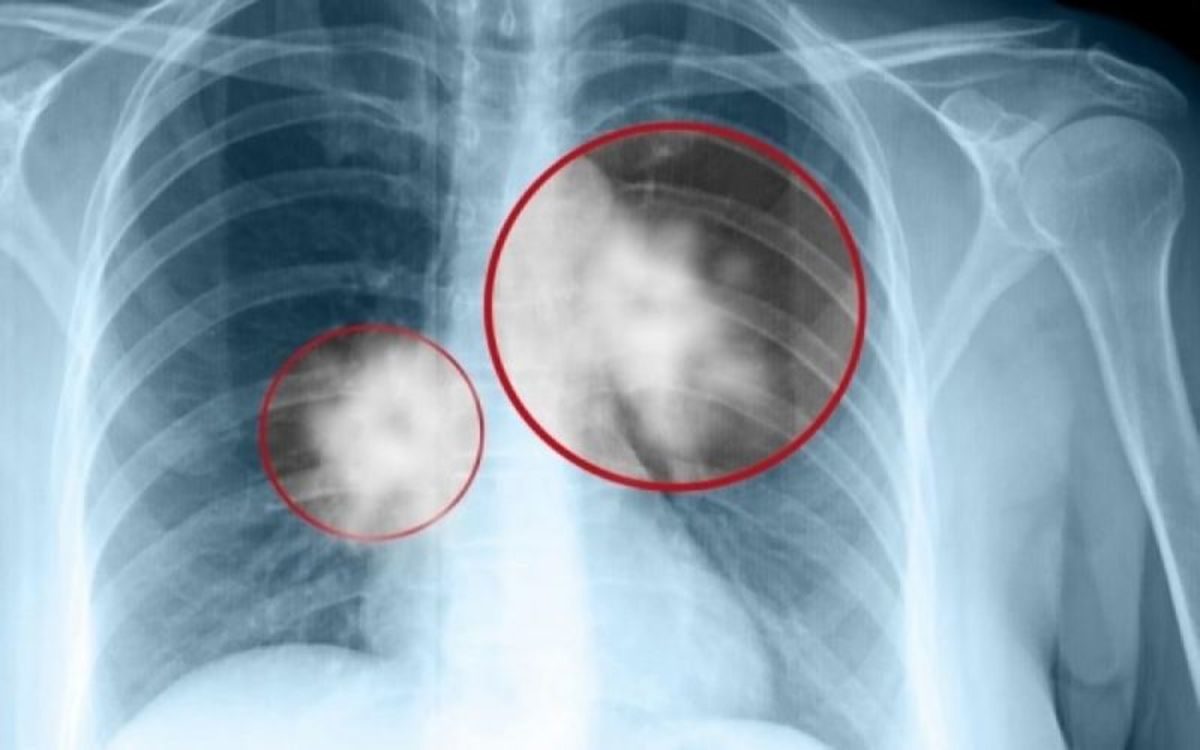

Καρκίνος πνεύμονα: Νέα ελπιδοφόρα αποτελέσματα από κλινική μελέτη

Άκρως εντυπωσιακά είναι τα αποτελέσματα της ενδιάμεσης ανάλυσης της νέας κλινικής μελέτης για την ανοσο-ογκολογική θεραπεία, pembrolizumab, σε ασθενείς με καρκίνο του πνεύμονα.

Το pembrolizumab σε συνδυασμό με  χημειοθεραπεία επέκτεινε σημαντικά την επιβίωση και σταμάτησε την εξέλιξη της νόσου σε ασθενείς με καρκίνο του πνεύμονα.